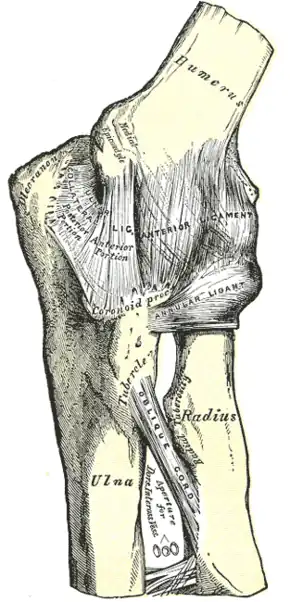

.jpg) Elbow joint. Deep dissection. Anterior view.

Elbow joint. Deep dissection. Anterior view. -

Left elbow-joint, showing anterior and ulnar collateral ligaments.

Left elbow-joint, showing anterior and ulnar collateral ligaments. -